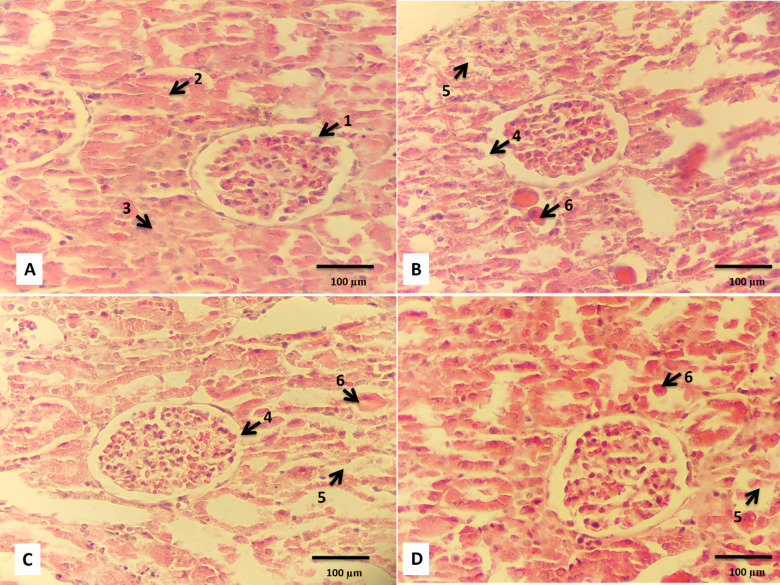

本研究旨在探讨人参根提取物对AKI大鼠顺铂肾组织损伤的影响及其参与的分子机制。将24只雄性Wistar大鼠随机分为4个实验组:对照组、顺铂组、提取物100 mg/kg组、提取物200 mg/kg组。研究时间为7 d,除对照组外,其余大鼠均于第4天给予顺铂单剂量10 mg/kg。我们的研究结果显示,与顺铂组相比,提取物组的血肌酐浓度显著降低。在顺铂组中,与对照组相比,观察到严重的肾脏组织病理学改变。在提取物组中,观察到的组织损伤明显小于顺铂组。人参提取物200与提取物100相比,组织损伤最小。与顺铂组比较,各提取物组p21、p27、p53、TIMP2、IGFBP7、NF-κB的表达均显著降低。我们的研究结果显示,给药人参提取物可改善顺铂诱导的AKI,并剂量依赖性地降低NF-κB基因表达和细胞死亡诱导基因。

This study is designed to assess the effect of root extract of P. ginseng on kidney tissue injury attributed to cisplatin and its molecular mechanism involved in this process in the AKI rat model. Twenty-four male Wistar rats were randomly allocated into 4 experimental groups including: the control group, the cisplatin group, the extract 100 mg/kg group, and the extract 200 mg/kg group. The duration of the investigation was 7 days, and all rats except the control group received a single dose of 10 mg/kg cisplatin on the 4th day. Our findings exhibited a significant reduction in blood concentration of creatinine in extract groups compared to the cisplatin group. In the cisplatin group, severe renal histopathological alterations were observed compared to the control group. In extract groups, significantly less tissue damage was observed than in the cisplatin group. Ginseng extract 200 showed minimal tissue damage as compared to extract 100. The expression of p21, p27, p53, TIMP2, IGFBP7, and NF-κB decreased significantly in extract groups compared to the cisplatin group. Our findings displayed amelioration of cisplatin-induced AKI and dose-dependent decrease of the NF-κB gene expression and cell death-inducing genes by administration of P. ginseng extract.